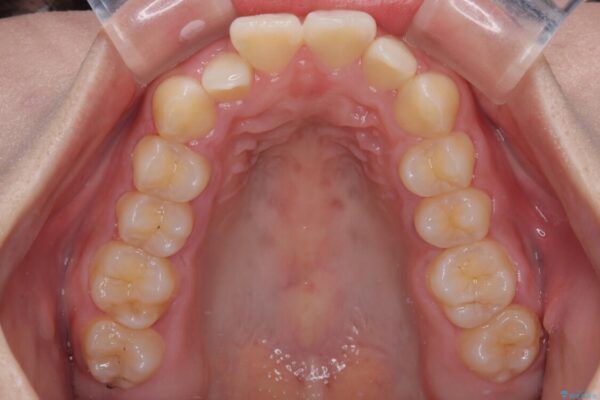

治療前

• 目立ちにくい表側装置で1年完了!狭いアーチを側方拡大し前歯のデコボコを整えた症例 治療前画像

前歯のデコボコが気になるでのことで来院された患者様です。

歯列アーチが狭くスペース不足により前歯がデコボコしている状態でした。見た目を改善しつつ、前歯を前方に突出させず、自然な笑顔を目指したいというご希望でした。